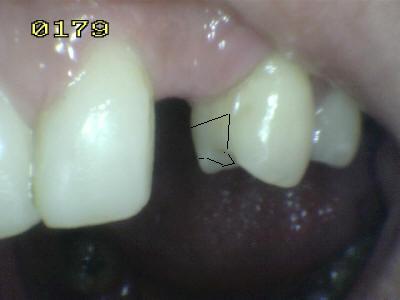

Vista vestibular. El matiz del

póntico (flecha verde) se determino con el primer premolar (flecha

marrón)